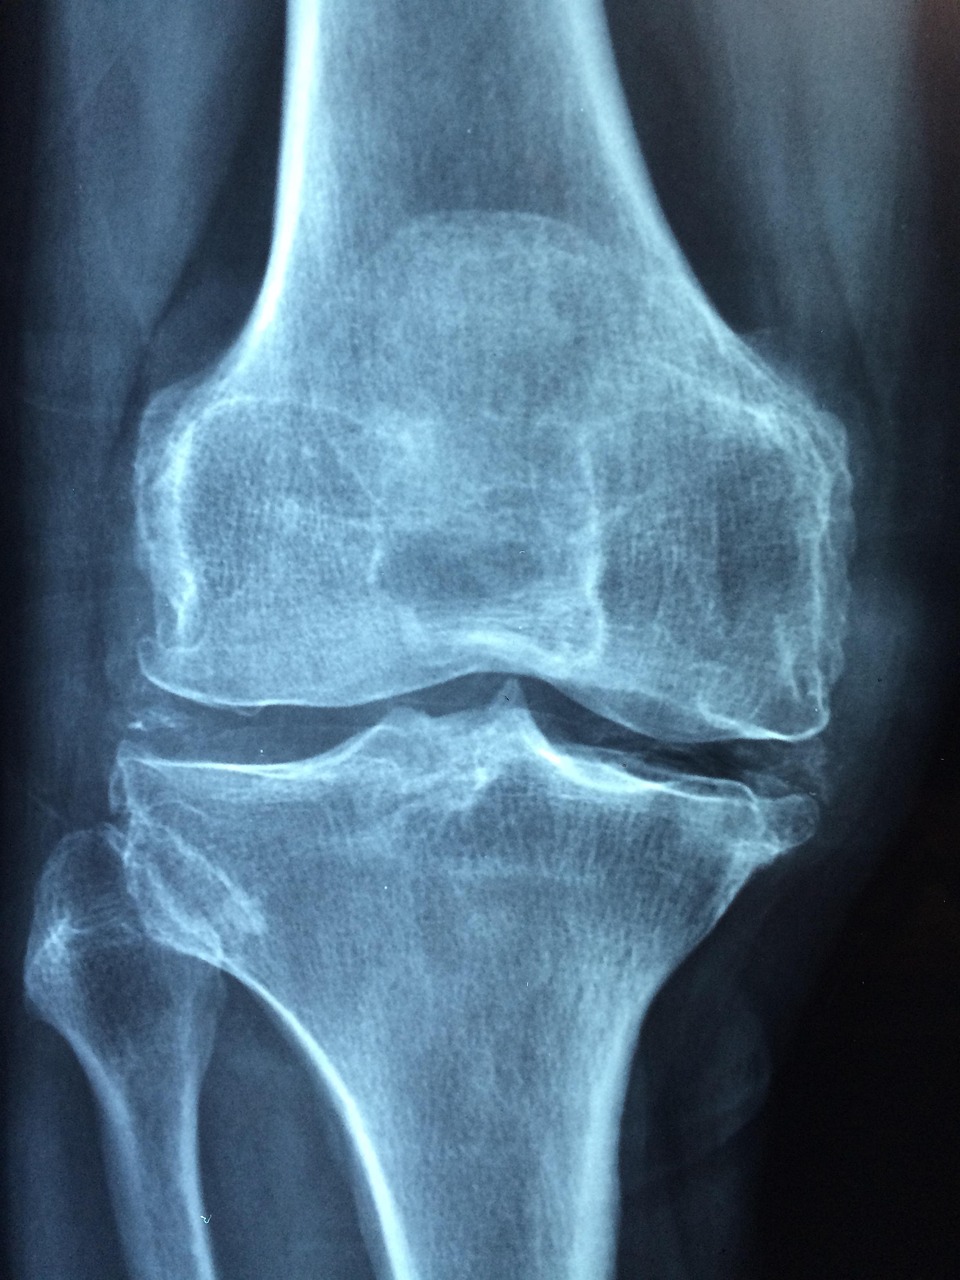

골밀도를 높이기 위해서는 체중 부하 운동이 필수입니다. 걷기, 계단 오르기, 가벼운 근력 운동은 뼈를 자극해 칼슘이 잘 정착되도록 돕습니다.

치료 후 6개월~1년은 재발 가능성이 높습니다. 정기적인 골밀도 검사와 생활습관 점검이 필요합니다.